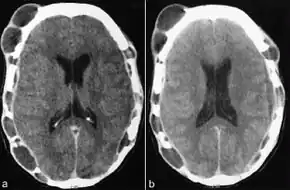

Tests usually include imaging using MRI.[5] Findings include breakdown of bone and thickening of the pituitary stalk. The perivascular space may appear prominent, the pituitary gland cystic and there may be signs in the white matter, a mass in the hypothalamus and enhancement of the meninges.[5]